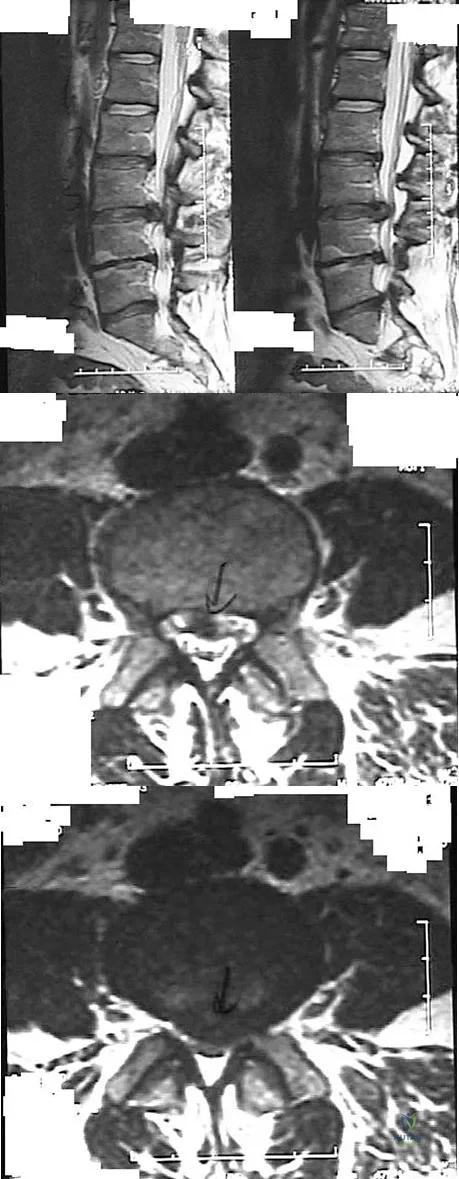

Question 76

Figures 28a through 28c show the MRI scans of a 30-year-old woman who weighs 290 lb and has low back and left leg pain. She also reports frequent urinary dribbling, which her gynecologist has advised her may be related to obesity. Examination will most likely reveal

Explanation